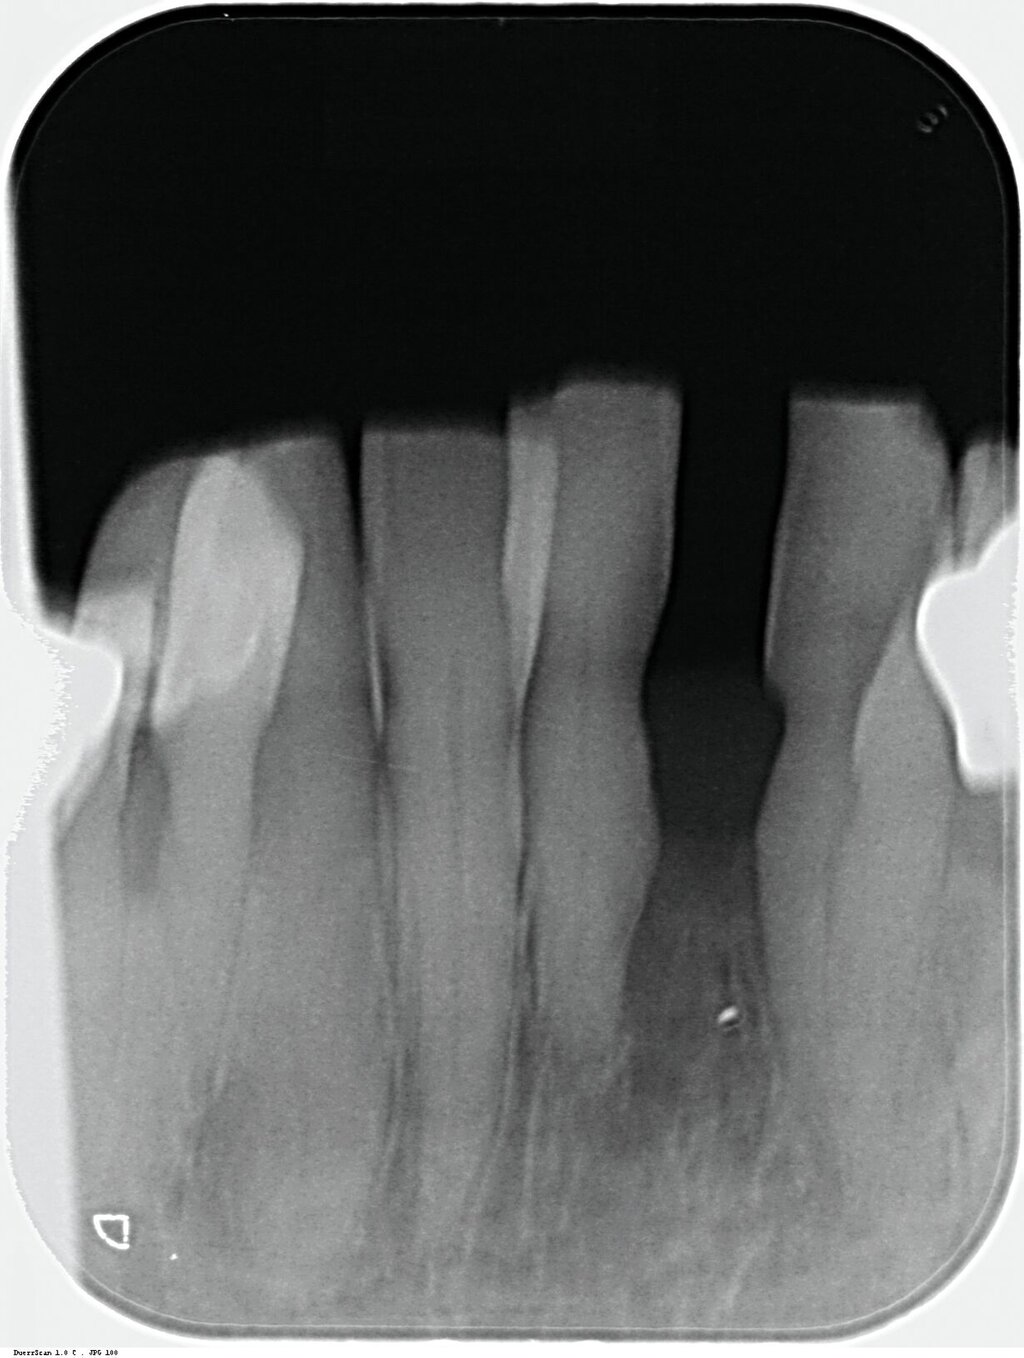

Da anhand eines Zahnfilms festgestellt worden war, dass der Zahn 31 – vermutlich aufgrund einer Paro-Endo-Läsion – eine apikale Aufhellung zeigte, war bereits die Extraktion mit anschließender Umarbeitung und adhäsiver Wiedereingliederung des extrahierten Zahnes als Option angesprochen worden. Kurz vor dem vereinbarten Eingriff meldete sich die Patientin telefonisch, um sich zu erkundigen, ob sie den Termin denn überhaupt noch benötige, da der betroffene, gelockerte Zahn 31 in der Unterkieferfront beim Essen von selbst herausgefallen sei und sie ihn bereits entsorgt habe. Schmerzen, eine Schwellung oder Nachblutungen verneinte die Patientin. Sie wurde gebeten, den vereinbarten Termin am Folgetag dennoch wahrzunehmen, mindestens zur Kontrolle der Wunde, gegebenenfalls zur Planung der Weiterversorgung (Abbildungen 5 und 6).